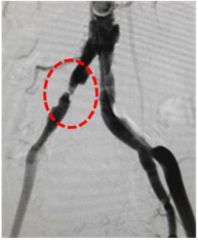

发现左侧上肢血压较右侧低伴活动性头晕2年,超声提示左侧锁骨下动脉狭窄伴随椎动脉反向血流。造影提示左侧锁骨下动脉完全闭塞:

治疗前